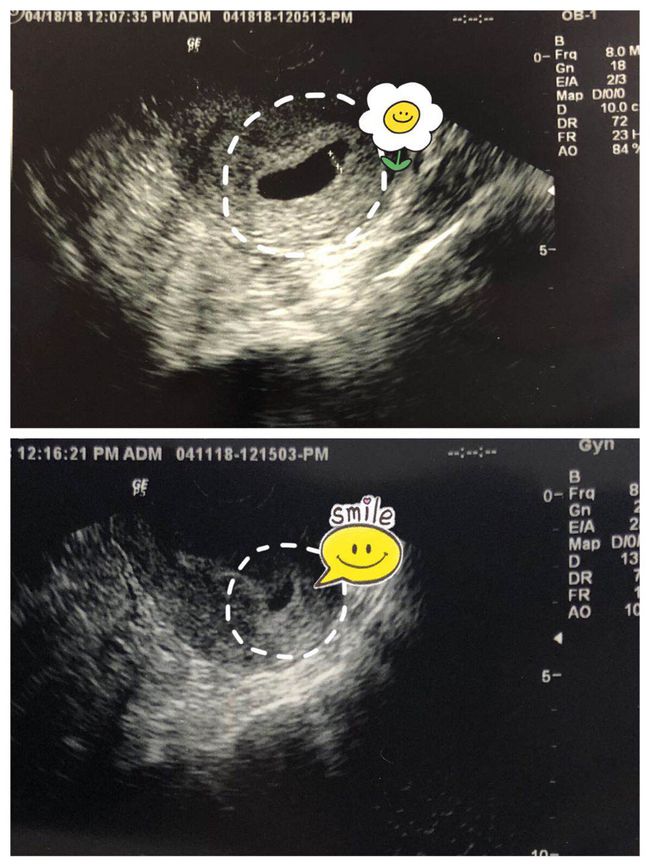

3. 稽留流产:指胚胎死亡后,胎儿及附属物未能及时排出,导致子宫内积血、感染等情况。

2. 手术治疗:对于稽留流产,医生会进行清宫术等手术治疗,将胎儿及其附属物排出。